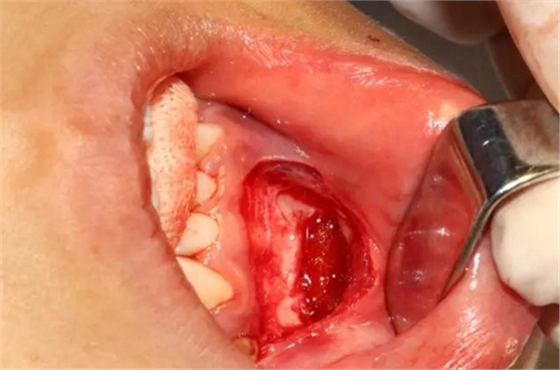

設(shè)計(jì)冠切的位置

橫斷牙冠,注意深度的把控

為了減少骨創(chuàng),“T”型分割牙冠

去除冠部